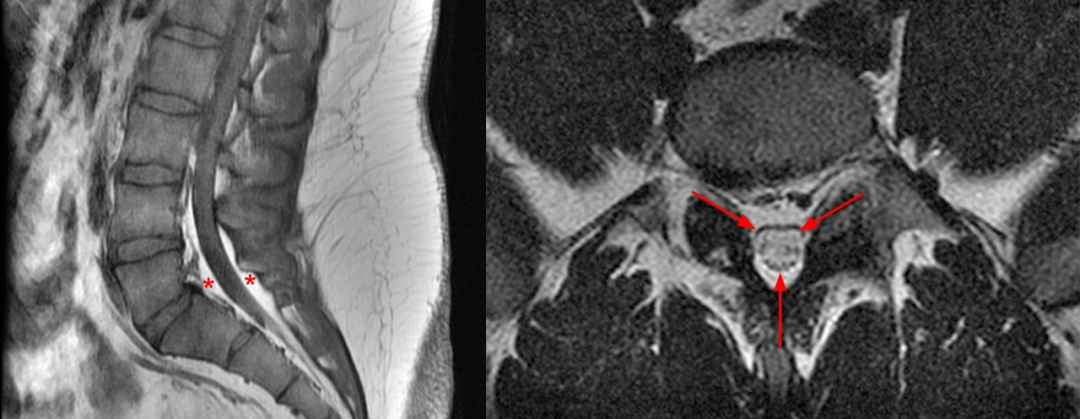

矢状位 T1WI 显示硬膜外脂肪组织的正常分布,在腰椎管主要分布于背侧,不连续,在每个椎体层交界处中断(星号)。S1 水平硬膜囊前方有少量正常脂肪组织(箭头),硬膜囊末端终止处,骶管内充满脂肪组织(蓝色星号)

正常的椎管内硬膜外脂肪分布,不会对椎管造成积压

大家得注意另外一种情况,椎管内硬膜外脂肪增多的同时合并节段性椎管扩大,此时虽然脂肪增多,但没引起硬膜囊受压,这不符合硬脑膜囊压迫证据的 SEL 标准。

内脏脂肪沉积明显(星号),而后方皮下脂肪组织正常(箭头),与内脏型肥胖相适应

53 岁,男,腰痛和双侧坐骨神经痛,MRI 显示 SEL(蓝色星号)。既有皮下肥胖,也有内脏肥胖。大网膜(长箭头)深至白线和腹筋膜(箭头),浅至横结肠(红色星号)。肝前脂肪垫明显向上(蓝色箭头)。

回头看第二个病例皮下和内脏脂肪沉积

在肥胖患者的腰椎 MR 图像上,经常发现位于皮下筋膜和深层脂肪层的局灶性水肿,这一发现没有已知的相应临床症状或意义,只是它可能被误认为是病理,并且被认为是由于深部脂肪组织中的筋膜间隔比浅部脂肪组织组织中的筋膜间隔组织较少且间隔更广,而浅部脂肪组织中的筋膜间隔分布更均匀、更紧密

回头看第二个病例同样存在深层脂肪的水肿